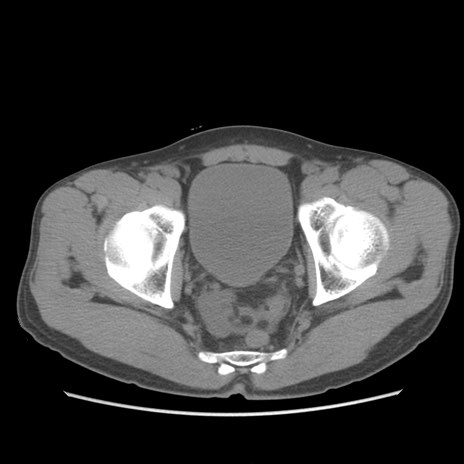

症例56 CT(横断像)

脂肪ウインドウ